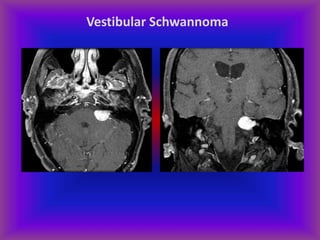

Vestibular Schwannoma